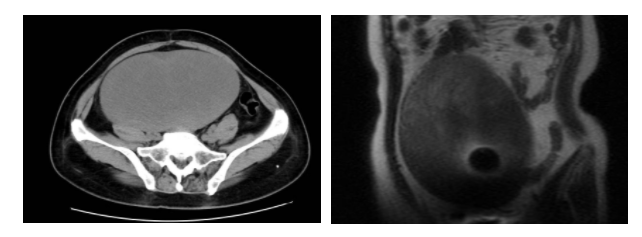

After her admission in the hospital, she underwent ultrasonic inspection, CT, MRI and other examinations with the following findings: a giant quasi-circular soft tissue mass shadow was present in the abdominal pelvic cavity with uneven internal density, the surrounding soft tissues were compressed and displaced, and there were small amounts of ascites in abdominal cavity. Her symptom inclined to be ovarian tumor.

The medical imaging results show that the enormous tumor occupied 80% of the abdominal cavity.